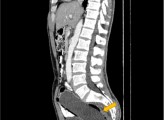

Ο άντρας φοβήθηκε τόσο πολύ την αντίδραση της συζύγου του που καθυστέρησε να ζητήσει βοήθεια για τρεις ημέρες. Όπως είπε στους γιατρούς αυτό συνέβαινε επειδή είχε μέσα του ένα μπουκάλι των 250ml. Το εντόπισαν μόνο όταν τον έστειλαν για αξονική τομογραφία. Γράφοντας στο περιοδικό «Clinical Case Reports», οι γιατροί είπαν ότι δεν ήθελε να αποκαλύψει ότι είχε βάλει το αντικείμενο μέσα του λόγω «αμηχανίας και φόβου για τη γυναίκα του».

Ο 50χρονος είχε σπρώξει πρώτα το κάτω μέρος του μπουκαλιού μέσα, ώστε να μπορεί να το βγάλει πιάνοντας το πάνω μέρος. Δυστυχώς, δεν μπόρεσε να βγάλει το αντικείμενο, αφήνοντας το πλαστικό μπουκάλι σφηνωμένο βαθιά μέσα στο παχύ έντερό του.